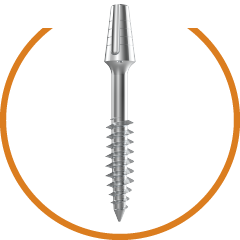

Progressive single spiral threads. Anti- rotational cuts to improve primary stability. Higher Bone Implant contact.. More Resistance to Tensile & Compressive forces. Surface treated thread to achieve better secondary stability.

Allow insertion in minimum 1-2 drilling. Optimum Zygomatic bone engagement. Micro-polished tip without any sharp edges.